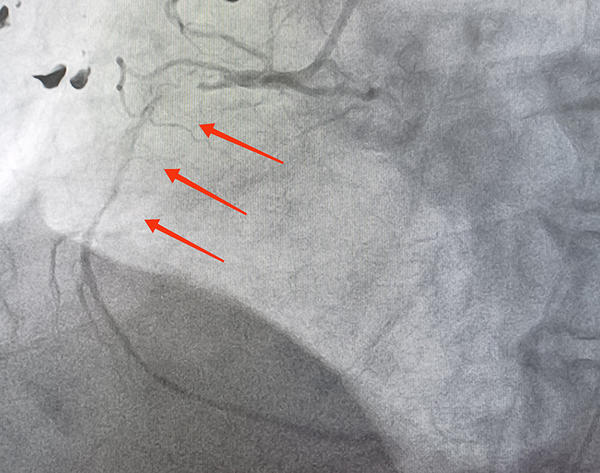

A 6Fr introducer sheath was placed in right common femoral artery and the coronary angiography revealed LAD with acute total occlusion and grade 5 thrombus in middle segment, normal LMCA and Circumflex. The RCA with 99% lesion in proximal segment and grade 4 thrombus with diffuse distal disease and TIMI 1 flow (Figures 3,4).

Figure 3: LAD with acute total occlusion and grade 5 thrombus in middle segment

Figure 4:RCA with 99% lesion in proximal segment and grade 4 thrombus with diffuse distal disease and TIMI 1 flow